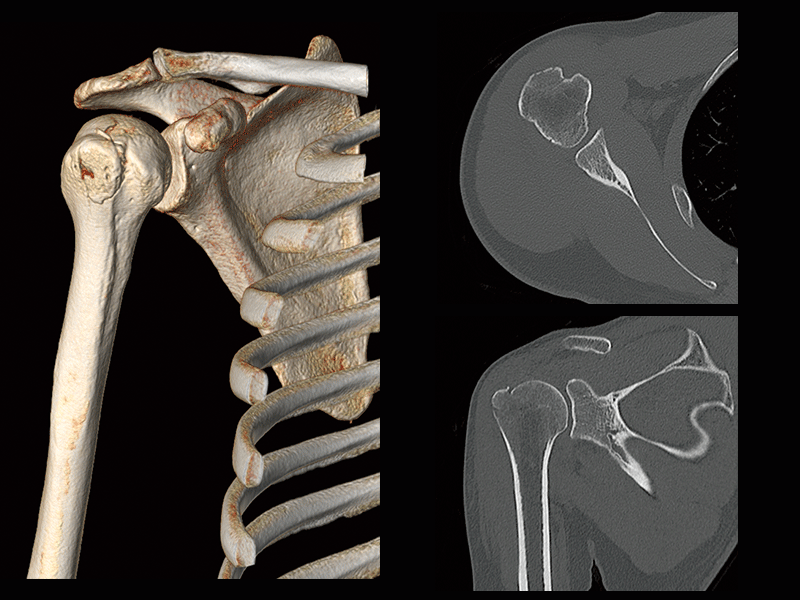

Humeral greater tuberosity fracture

- * Images other than axia images were processed by the 3D image analysis system SYNAPSE 3D.